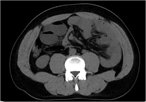

First reported case of paratesticular seminoma in a postpubertal cryptorchid testis

Imad Elhajjar and others

Journal of Surgical Case Reports, Volume 2017, Issue 6, June 2017, rjx088, https://doi.org/10.1093/jscr/rjx088